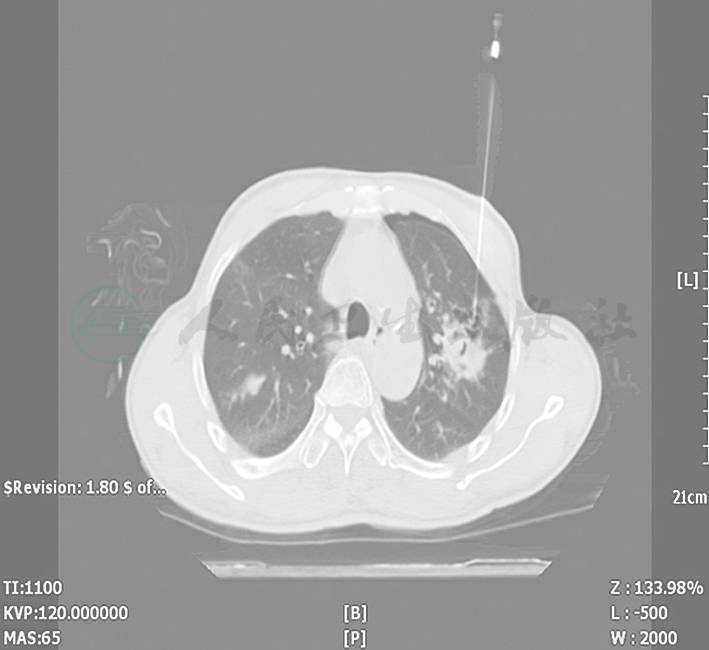

辅助检查:血常规:WBC 14.03 × 109/L,N 70.74%,L 21.84%,Hb 122g/L。尿葡萄糖阴性;尿酮体(+)。血气分析:pH 6.765;氧分压167mmHg;二氧化碳分压12.4mmHg;实际剩余碱?32.7mmol/L;实际碳酸氢根1.7mmol/L;阴离子隙25.9mmol/L。血浆乳酸> 12mmol/L(鼻氧管吸氧,氧浓度3L/min)。血葡萄糖5.4mmol/L;血尿素氮9.7mmol/L。凝血酶原时间15.30秒;活化部分凝血活酶时间78.20秒;凝血酶时间86.9秒;D-二聚体0.51mg/L。B型脑钠肽339pg/ml;心肌酶谱:心肌肌酸激酶153U/L;α-羟丁酸脱氢酶252U/L;谷草转氨酶136U/L;肌酸磷酸激酶2235U/L;乳酸脱氢酶339U/L。心电图检查:窦性心律不齐,左心室肥厚,部分导联ST段改变,QT间期轻度延长。腹部立位片未见异常。胸部CT见肺内多发斑片状高密度影,边缘粗糙(图1)。

图1 入院时胸部CT可见肺内多发斑片状高密度影,边缘粗糙